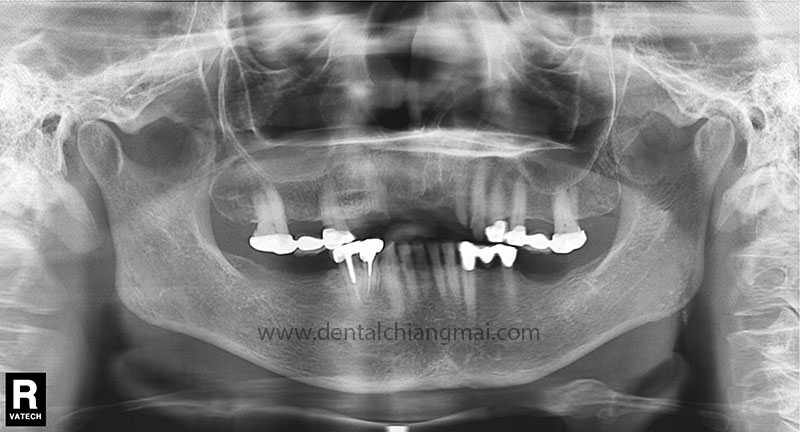

CASE 1 : 5 implants with 3 unit Bridges on upper front maxilla.

Before: